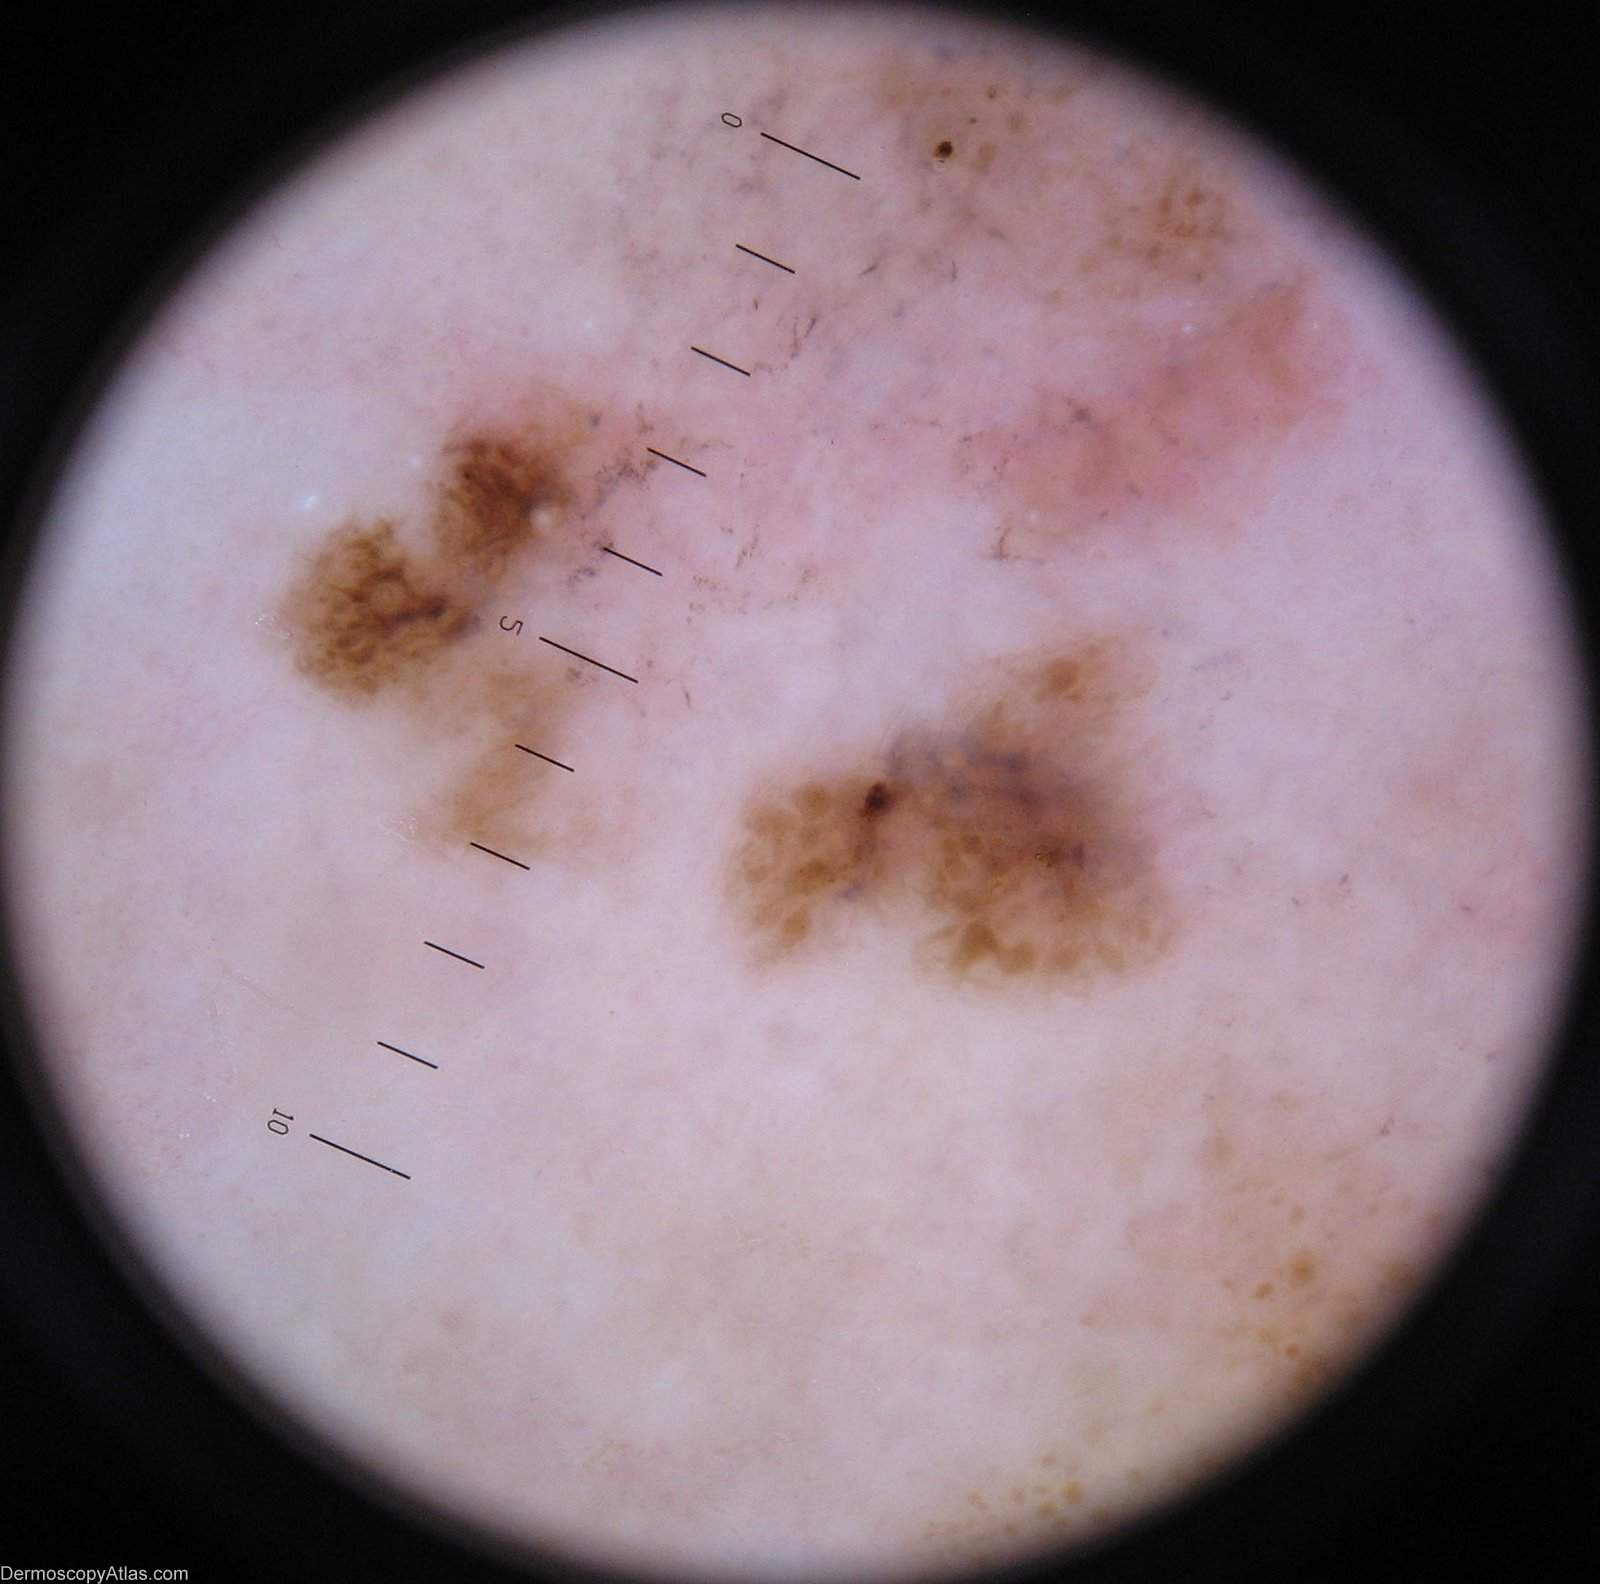

Image Number #2270 (Melanoma regression)

Site: Calf

Diagnosis: Melanoma regression

Description: Lesion on the calf. Clinically areas of regression are shown in both the pale and grey areas

Case courtesy of Dr Greg Canning  This poorly demarcated lesion is approx 5 cm in diameter and has resided on the left proximal postero medial calf of it's 72 year old owner for as long as she can remember. On reflection however she thinks it may have enlarged somewhat over the years. She has been repeatedly reassured about it by the doctors who have treated her numerous non melanoma skincancers.

Histopathology of incisional biopsy  There is an atypical melanocytic lesion composed of disparate foci separated by zones of regression. There are moderately to markedly atypical melanocytes forming irregular junctional nests and invading the epidermis. A lichenoid dermal inflammatory infiltrate is present and there are two foci of superficial nvasion of the dermis to the interface of papillary and reticular dermis. The Breslow thickness in each case is 0.4 mm. Mitoses are rare. The minimum clearance of the invasive components is 2.5 mm from the 3 o'clock margin. Atypical junctional nests almost abut the 3 o'clock edge.

The degree of regression obfuscates interpretation of the precursor lesion, but lentiginous activity is seen and involvement of a hair follicle. In combination with the multifocal nature of the lesion it

is likely that this is lentigo maligna melanoma.